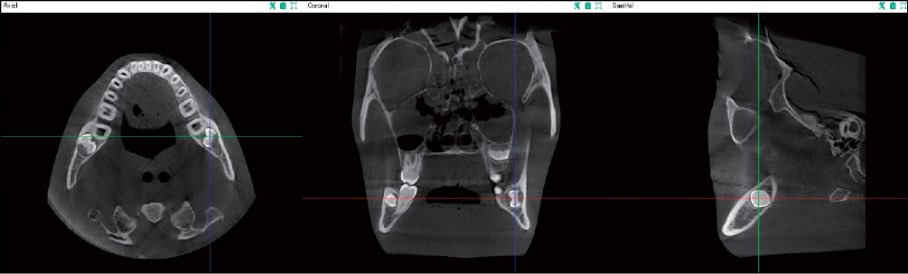

MPR(Multi-Planar Reconstruction)

MPRビューアーでは、診断エリアの3方向の断面画像(Axial, Coronal, Sagittal)を1画面に表示します。